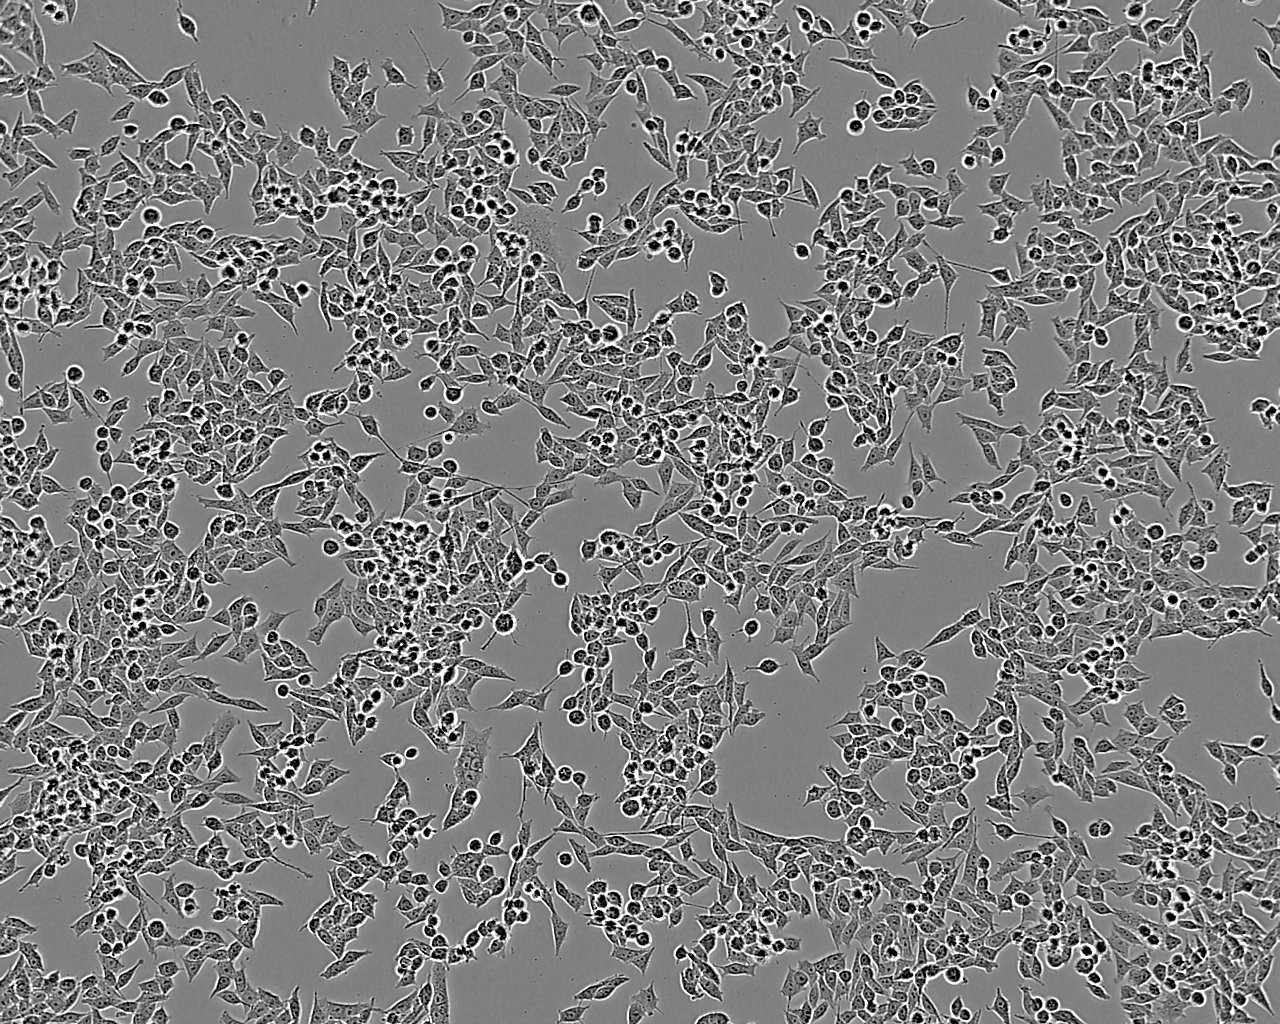

B95a is a derivative of the cell line B95-8 and was adapted to growth in adherence to the substrate surface. The parent line B95-8 was derived from a cotton-top marmoset (Saguinus oedipus). The B-lymphoblastoid cells are transformed with Epstein-Barr virus (EBV). B95a has been reported to be 10,000-fold more sensitive to measles virus present in clinical specimens than Vero cells and are useful host cells for the isolation of measles virus.

Split sub-confluent cultures (70-80%) 1:3 every 3-4 days using 0.05% trypsin or trypsin/EDTA; 5% CO₂; 37°C; cells grow initially as a monolayer, but will pile up and detach in maintenance medium.

Semi-adherent